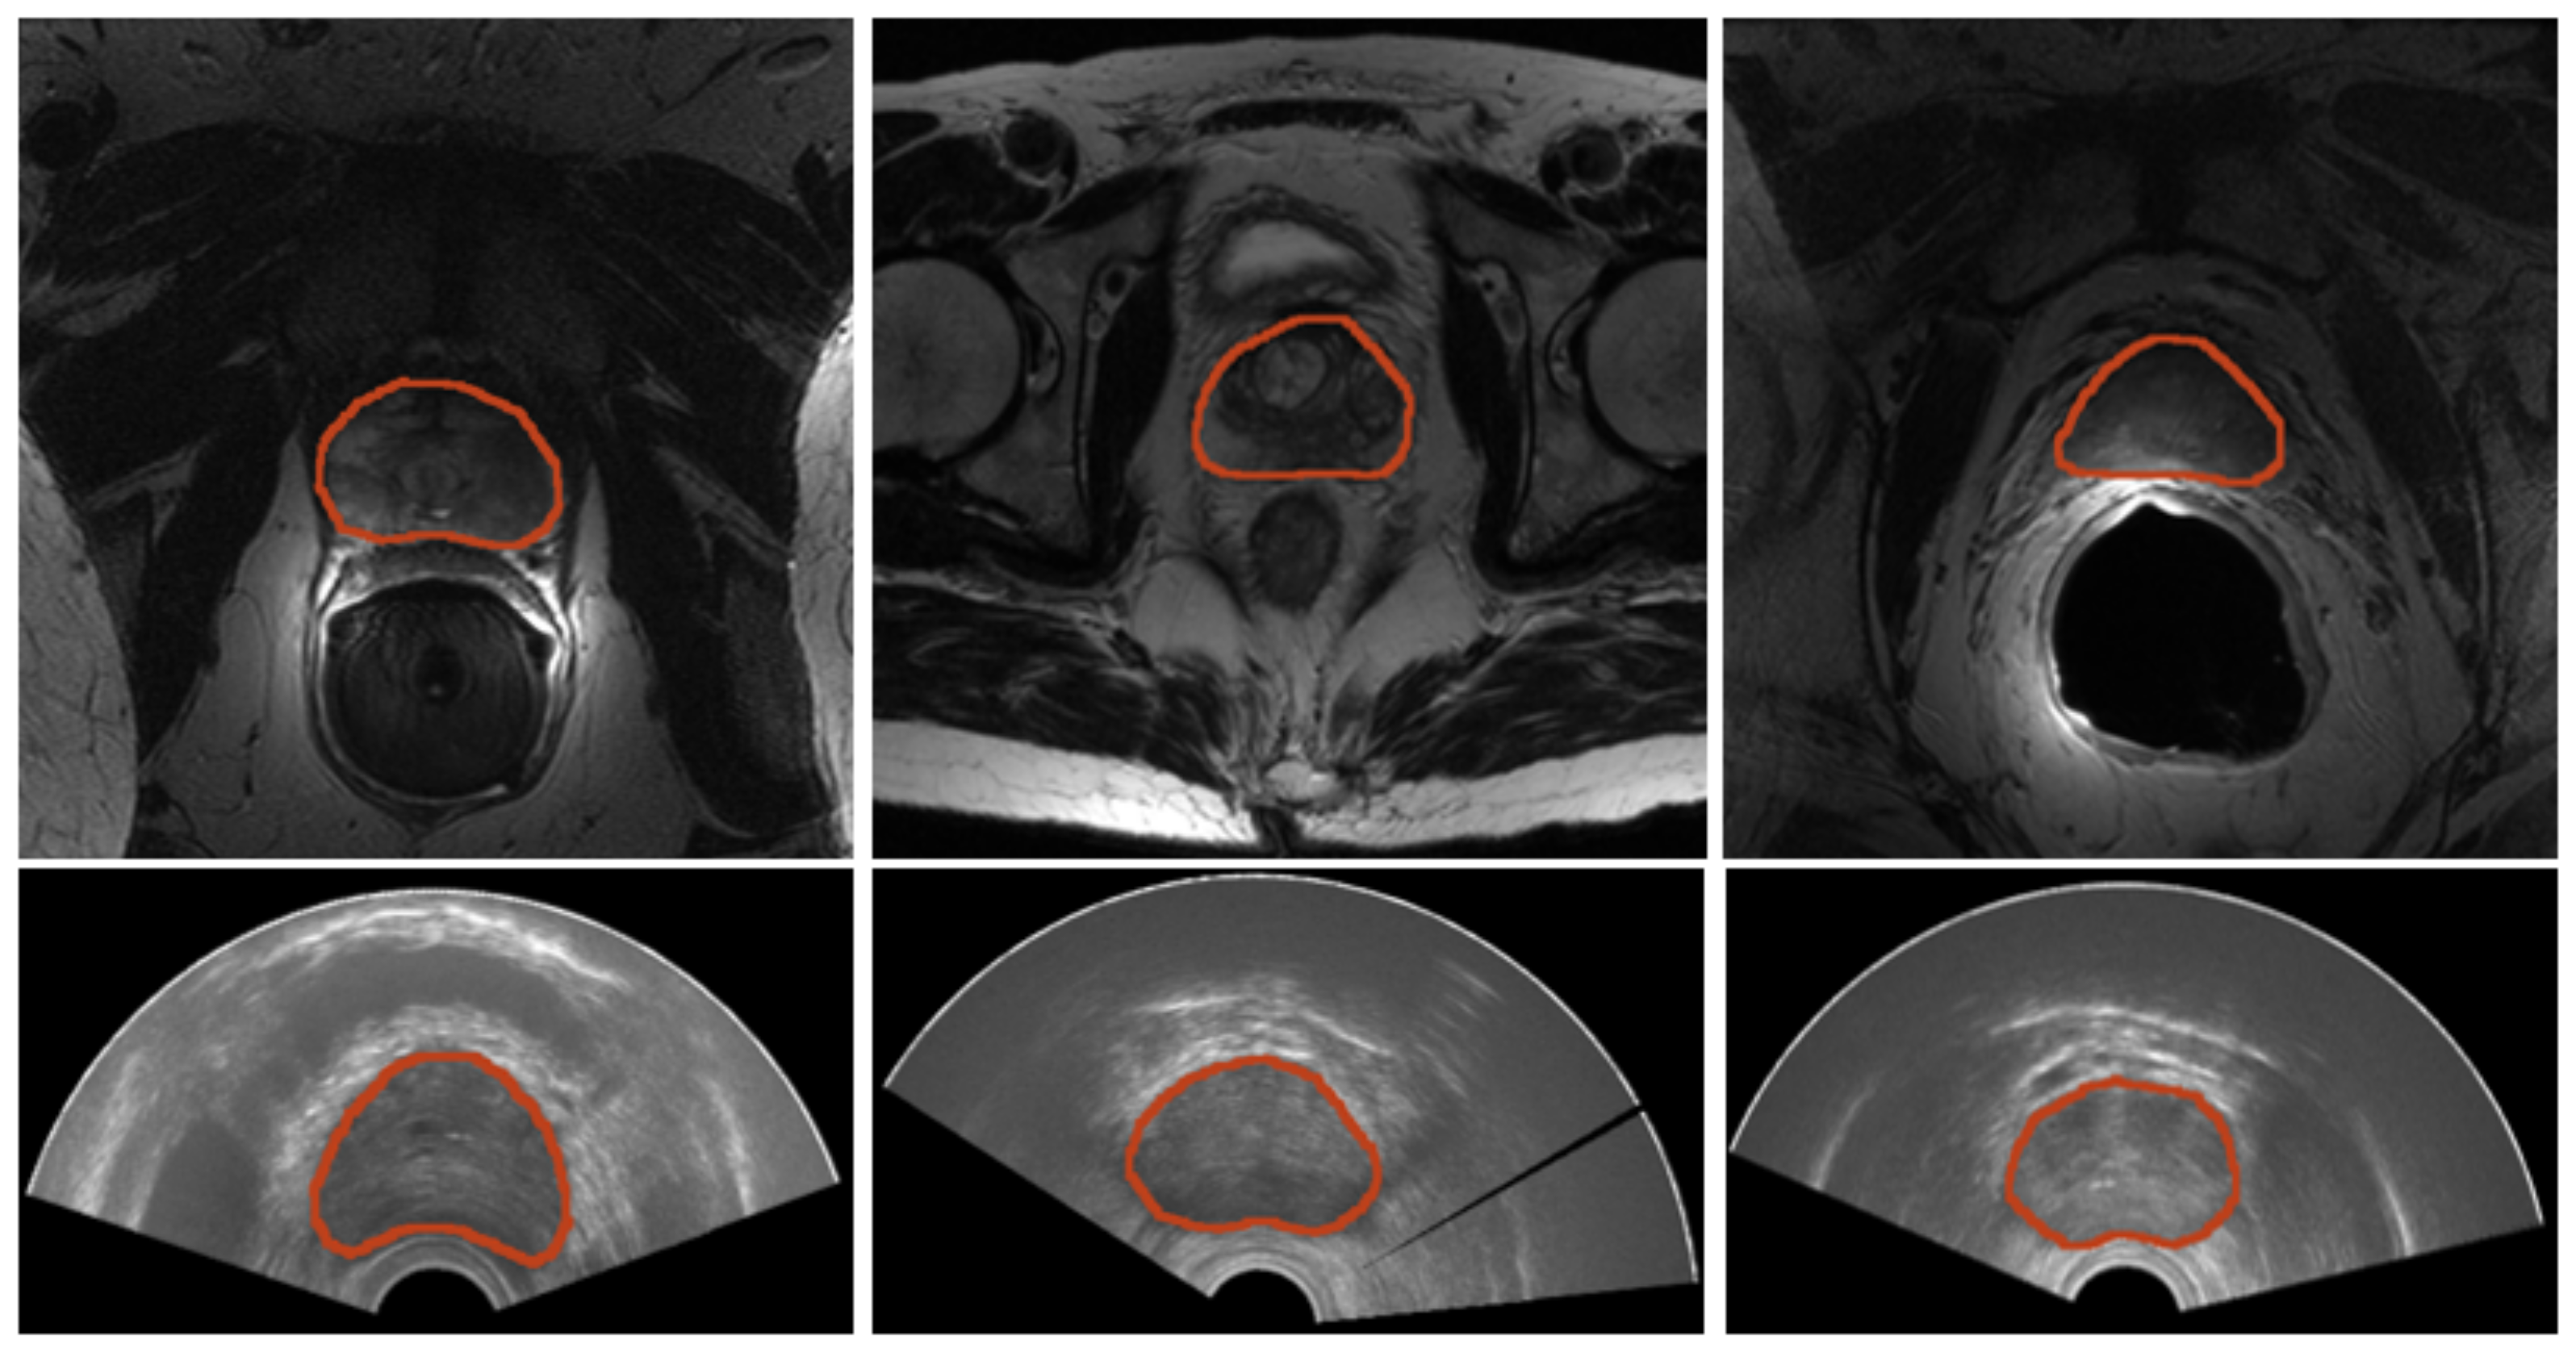

Sample images for both domains, TRUS and MRI, are reported in Figure 2. A summarized table for the considered materials is provided in Table 1.

Figure 2.

Samples of images from both modalities. (Top) Prostate MRI. From left to right, a sample image for each of the datasets—PROMISE12, SAML, and ZENODO—is shown. (Bottom) Three sample prostate TRUS from the ZENODO dataset.